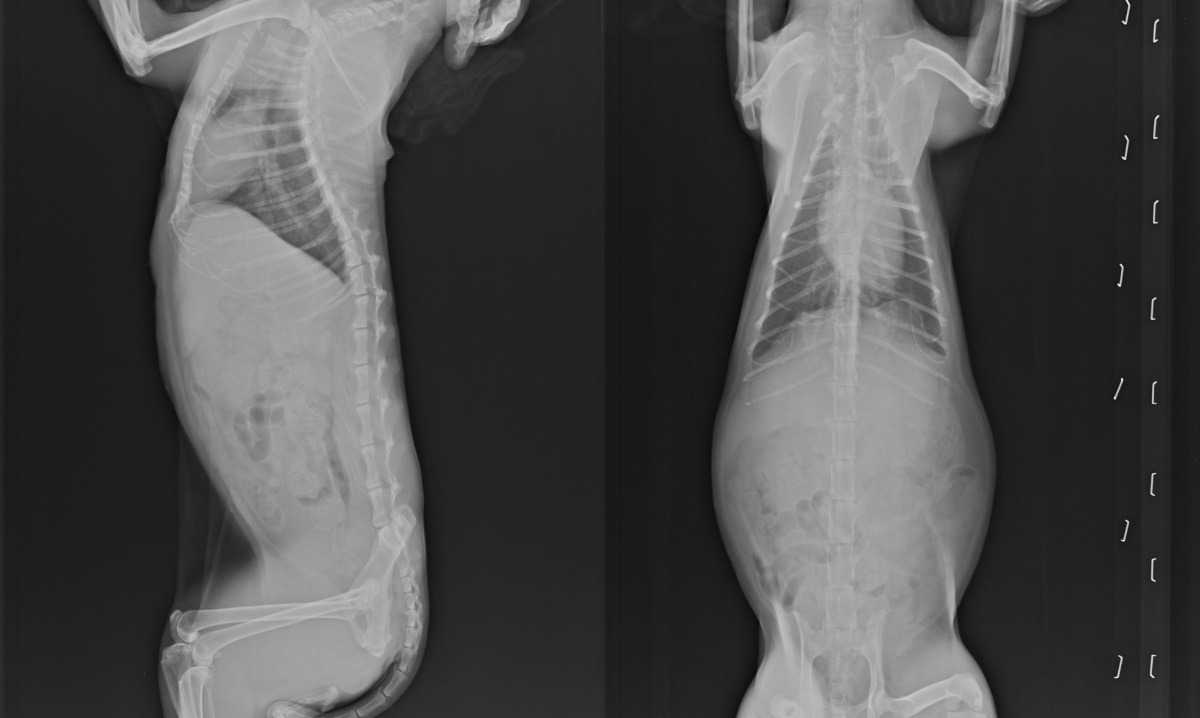

主題: 惡性乳房腫瘤化療 申請者姓名: 臺北市支持流浪貓絕育計劃協會 花色: 申請日期: 2013-11-21 12:22:09 申請者部落格: 申請者臉書網址: 所在縣市/合作醫院: 台北市/極光動物醫院 治療費用: 15655元 需求人數: 17人 已結案 (2014-01-10 17:43:28) 報名人員: Sunny Chen(已付款)、戴戴(已付款)、Chloe Liang(已付款)、Kero Yen(已付款)、juno(已付款)、Patrick(已付款)、余娉婷(已付款)、KiKi(已付款)、Tien-Yin Ku(已付款)、Sheirly Chu(已付款)、Moon(已付款)、謝雨妡(已付款)、sbjenny(已付款)、Emily Chou(已付款)、Wilson Hu、蘇小吉(已付款)、ERic YU(已付款)、claire chen(已付款)、 候補人員: 動物病情說明: 中和市保健路一隻不斷生育的母貓,四年來生了不少小貓,每次懷孕狀況就愈來愈差,已經沒有辦法打理自己,指甲深深的插入指頭裡行走不便,感覺越來越虛弱,志工前往協助捕捉終於在8/7日順利捕捉,送醫發現貓咪有乳房腫瘤,經討論決定先手術摘除單側乳房送化驗,術後狀況良好,也長胖,8/24日貓咪突然不吃不喝,經檢驗腎指數超標機器無法檢驗出,狀況急速惡化,緊急通知餵養人前往探視,當天貓咪受到鼓舞,開始進食,一周後腎指數穩定,雖然報告顯示是惡性腫瘤,復發率極高,我們仍希望在最後的日子讓貓咪舒服快樂,目前每天需打水125CC定期回診監控指數,X光追蹤是否轉移,醫療費用還請大家幫忙。

兩次回診發現天空都有慢慢變胖,指數穩定,但觸診卻發現上次手術部位腫瘤已經擴散他其他乳房上,X光檢查並不明顯,考慮天空目前狀況穩定,決定進行單側全乳房摘除手術,術後天空非常爭氣,恢復狀況良好,腎指數也降至CRE 2.5,BUN35,不需要再天天打水,前天拆線狀況很好,目前等休養再進行另一側泉乳房摘除術。

10/10在拆線前夕照顧員發現天空包紮的紗布有脫落並且有怪怪的味道,送至醫院拆開紗布,發現有不明滲出液,將黏稠的液體刷除後,拆線仔細檢察傷口,發現並不是從縫線感染滲出,有可能是彈性繃帶勒傷後肢所以有少許滲出液,回協會繼續觀察,並保持傷口乾燥,隔天依舊有很多黏稠的液體,刷洗效果不佳,隔天狀況越來越糟糕,緊急又回診,醫師懷疑可能是腫瘤轉移到皮膚,恐怕第二階段乳房切除要暫停,先以類固醇治療,再仔細評估是否要進行化療,住院第一天白血球27400有感染的狀況,腎指數也稍稍上升,但食欲胃口還是很好,大吃大喝的,但還是每天需要打125cc輸液,幾日觀察治療下,沒有再出現組織液滲出的狀況,先帶回協會安置,在持續回診追蹤化療。

10/19天空出院之後每天持續施打輸液125CC,兩天施打一次EPO,每周追蹤狀況越來越穩定,但另一側乳房開始出現小小顆粒的腫塊,卻因為白血球偏高又貧血,沒有辦法進行手術,決定先以\療的方式控制,等身體機能恢復在考慮是否需要進行另一側全乳房摘除,過程天空非常的配合,儘管有不舒服他還是努力的把飯飯吃完,表現的精神奕奕,最喜歡吃鮮食,每次煮魚煮蝦一定吃光光,令人很欣慰,看到天空還在努力著,我們怎麼能放棄呢?

兩次化療後天空狀況越來越好,小顆粒的腫瘤已經消失,皮膚也沒有滲出液,現在就等一個月後,追蹤腫瘤變化和身體機能等指數再進行評估。